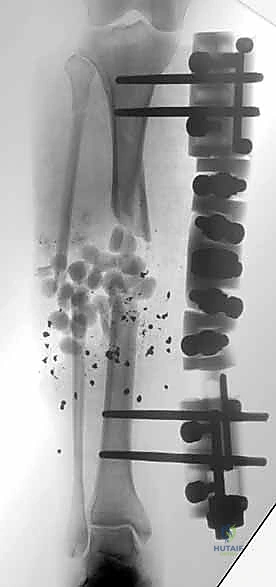

- الطلقات النارية وإصابات الحروب: والتي تسبب تهتكاً واسعاً في العظام والأنسجة الرخوة والأوعية الدموية.

هنا تبرز براعة هذا الإجراء. يتم إدخال دبابيس معدنية (Pins) في العظم السليم فوق وتحت منطقة الكسر، ثم تُوصل هذه الدبابيس بإطار معدني خارجي (Frame) خارج الجلد.

3. إدخال الدبابيس (Pin Placement)

باستخدام جهاز الأشعة السينية المتحرك داخل غرفة العمليات (C-arm)، يقوم الدكتور هطيف بتحديد الأماكن الآمنة (Safe Corridors) لإدخال الدبابيس المعدنية (Schanz pins). هذه الأماكن يتم اختيارها بدقة متناهية لتجنب إصابة الأعصاب أو الأوعية الدموية الحيوية في الساق. يتم عمل شقوق صغيرة جداً في الجلد وإدخال الدبابيس في العظم السليم فوق وتحت الكسر.

5. تركيب الإطار الخارجي (Frame Assembly)

بمجرد أن تصبح العظام في الوضع الصحيح، يتم توصيل الدبابيس البارزة من الجلد بقضبان معدنية (Rods) أو إطار دائري باستخدام مشابك (Clamps) خاصة. يتم إحكام ربط هذه المشابك لتثبيت العظام بقوة ومنعها من الحركة تماماً.

6. إغلاق الجروح والتغطية

إذا كان هناك جرح مفتوح، يُترك مكشوفاً أو يُغطى بضمادات خاصة (مثل جهاز الشفط السلبي VAC) للسماح بالعناية به في الأيام التالية، أو يتم إجراء ترقيع جلدي (Skin Graft) إذا لزم الأمر.